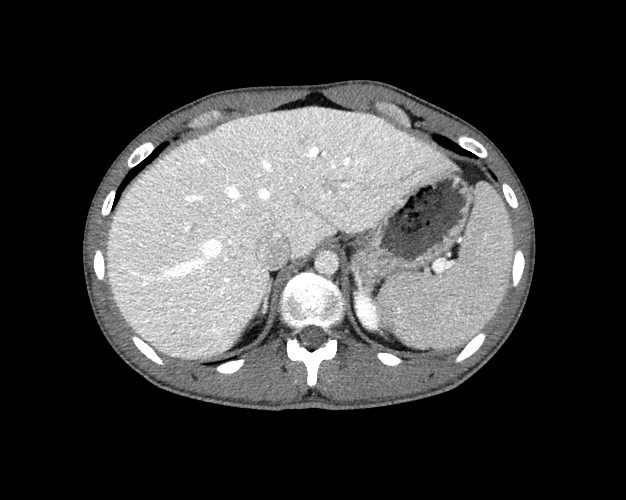

Body

Covers abdominal CT anatomy.